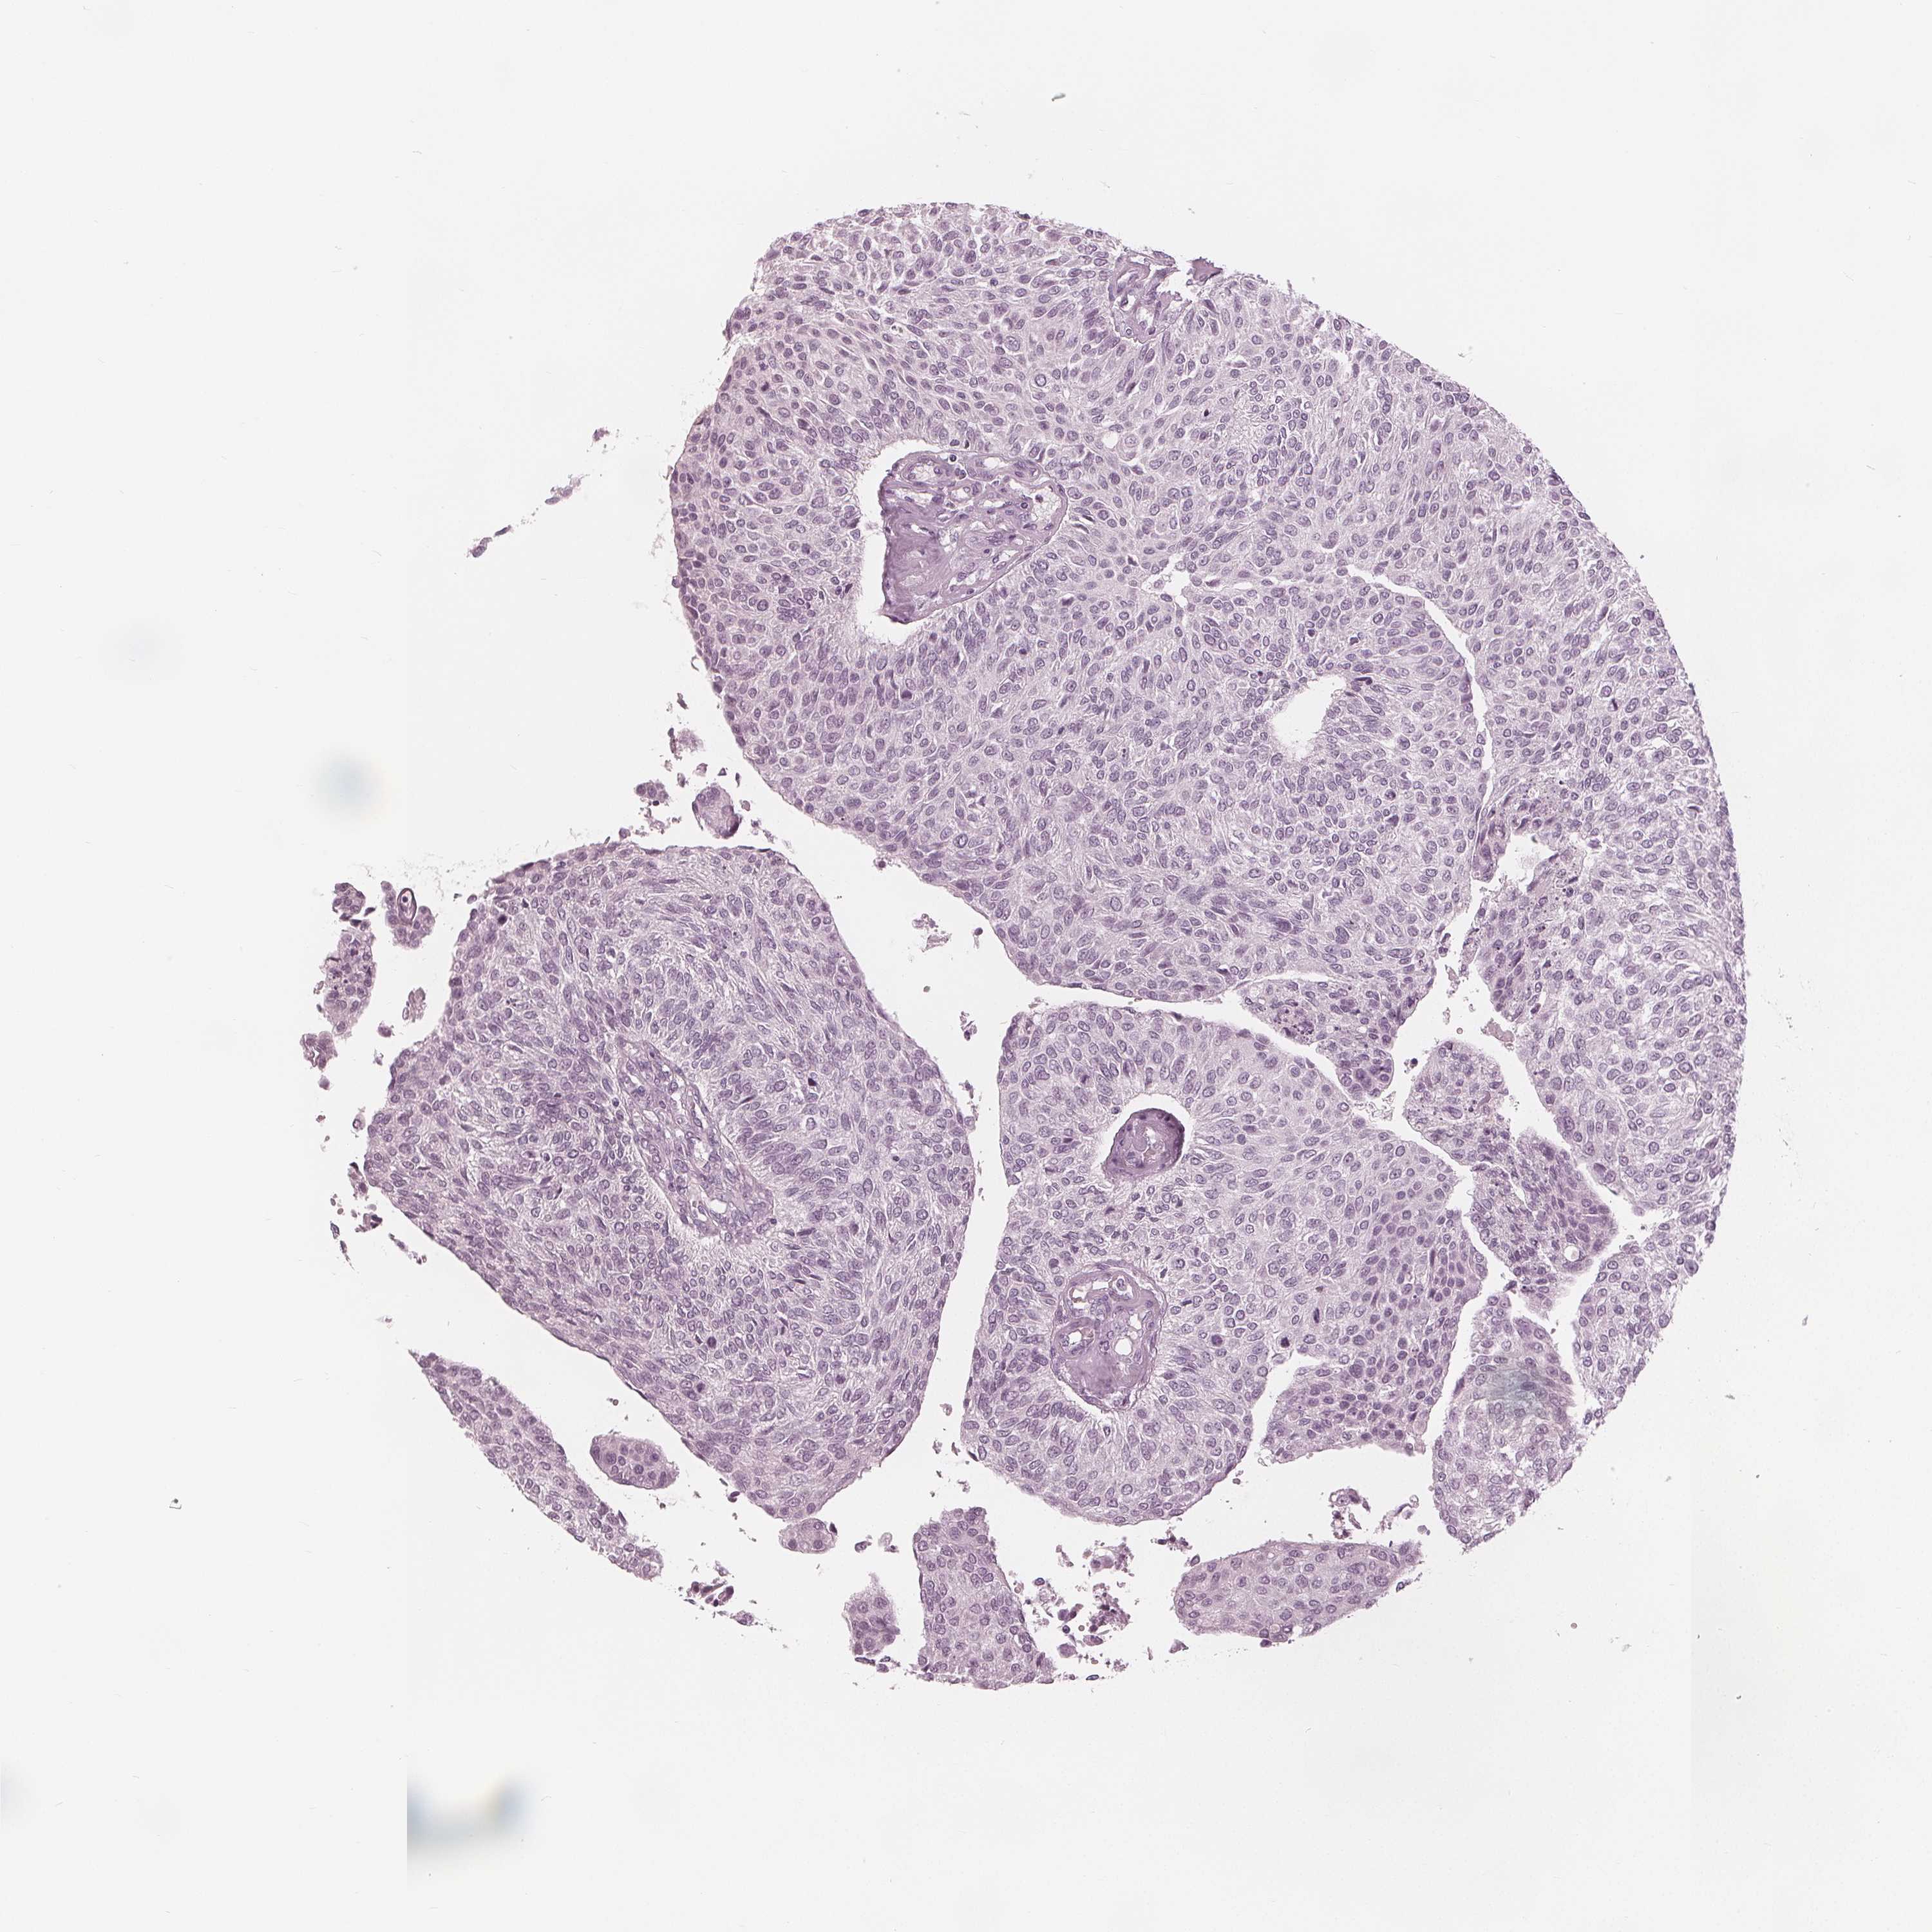

UROTHELIAL CANCER - Protein expressioni

A mouse-over function shows sample information and annotation data. Click on an image to view it in a full screen mode. Samples can be filtered based on level of antibody staining by selecting one or several of the following categories: high, medium, low and not detected. The assay and annotation is described here.

Note that samples used for immunohistochemistry by the Human Protein Atlas do not correspond to samples in the TCGA dataset.

Antibody stainingi

Antibody staining in the annotated cell types in the current human tissue is reported as not detected, low, medium, or high, based on conventional immunohistochemistry profiling in selected tissues. This score is based on the combination of the staining intensity and fraction of stained cells.

Each image is clickable and will lead to virtual microscopy that enables deeper exploration of all samples and also displays staining intensity scores, fraction scores and subcellular localization as well as patient and tissue information for each sample.

Antibody HPA020108

Antibody HPA029473

Antibody CAB016762

Urothelial carcinoma, High grade

Urothelial carcinoma, NOS

Urothelial carcinoma, Low grade